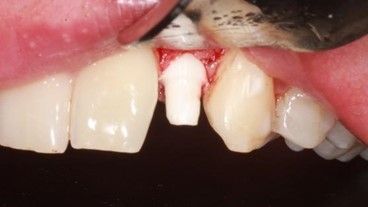

Para realizar el procedimiento quirúrgico, se realizó el bloqueo del nervio alveolar superior anterior y del nervio nasopalatino. Se realizó una incisión intrasulcular, desde la superficie distovestibular del incisivo central superior izquierdo hasta la mesiovestibular del canino superior izquierdo, para colocar un implante de circonia Z System® (Oensingen, Suiza) de 3.6 x 10 mm (Fig.7). La última fresa empleada fue de 3 mm de anchura (Fig. 8) para conseguir una estabilidad primaria de 35 Ncm y, posteriormente se suturó el colgajo con Supramid® (Barcelona, España) 5/0 mediante puntos simples.